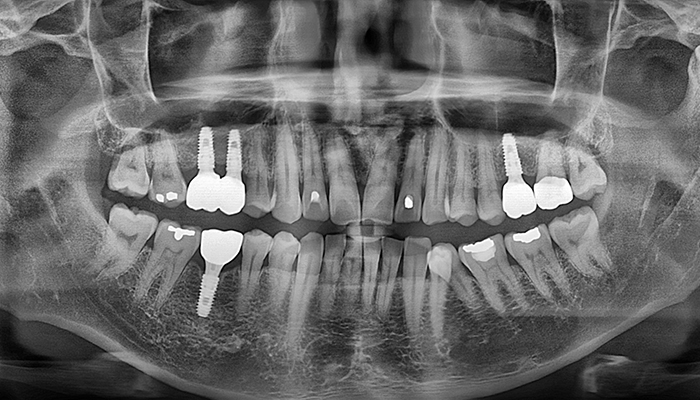

뼈이식 / 임플란트 식립공간 확보

잇몸을 절개하고 난 후 뼈를 넣고 상악동을 들어 올릴만한 작은 통로를 만들어 뼈이식할 공간과 임플란트 식립할 공간을 확보합니다.

잇몸 뼈이식 시술 진행

들어올린 빈 공간에 뼈를 이식하는데 이때 사용되는 뼈이식 재료로는 자가치아뼈, 자가골, 인공뼈, 합성골 등이 있습니다.

임플란트 매식체 식립

잔존하고 있는 잇몸뼈의 양에 따라 뼈이식과 동시에 임플란트 식립하기도 하고 6-9개월 후 식립하기도 합니다.